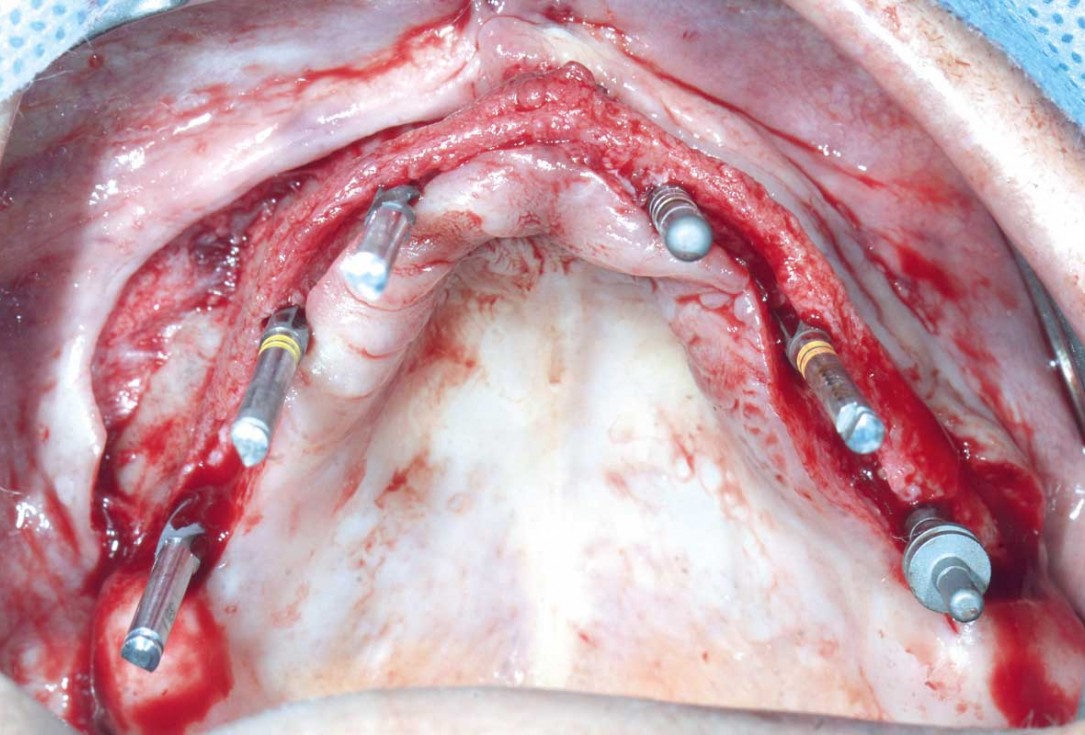

Full arch GBR using cerabone®, maxgraft® and Jason® membrane with simultaneous implantation of 6 Straumann® implants - Dres. A. Signorio and G. Molina